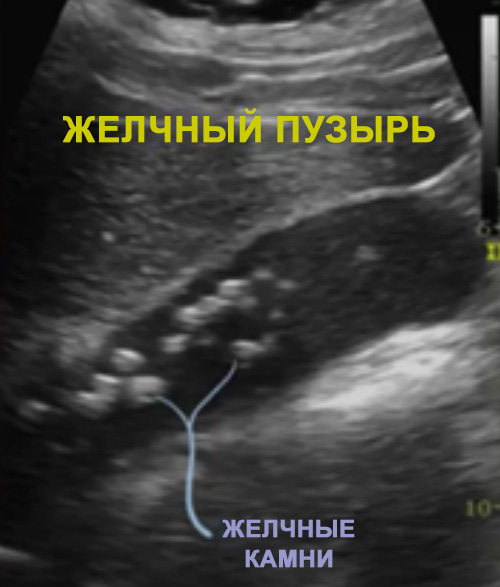

УЗИ желчного пузыря

Типичными признаками холецистита при ультразвуковой диагностике являются: